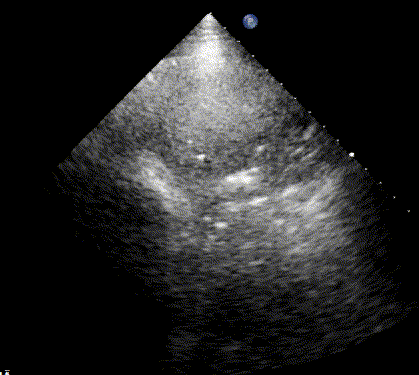

Tissue-like Lung Pattern

As the air content of the lung decreases, the ultrasound image begins to resemble that of solid tissue, since the absence of air artifacts allows ultrasound waves to penetrate more deeply. When all air is replaced by fluid or inflammatory material, the affected lung often appears similar in echotexture to the liver, a phenomenon known as hepatization.

This tissue-like lung pattern indicates dense consolidation and is typically associated with severe pneumonia or atelectasis. For example, the latter may result from airway obstruction (e.g., by a mucus plug) or extrinsic compression (e.g., from a large pleural effusion).

As fluid accumulation or parenchymal consolidation progresses, the ultrasound findings typically evolve in the following sequence: → Multiple B-lines → Confluent B-lines → Subpleural consolidation → Shred sign → Dense consolidation.